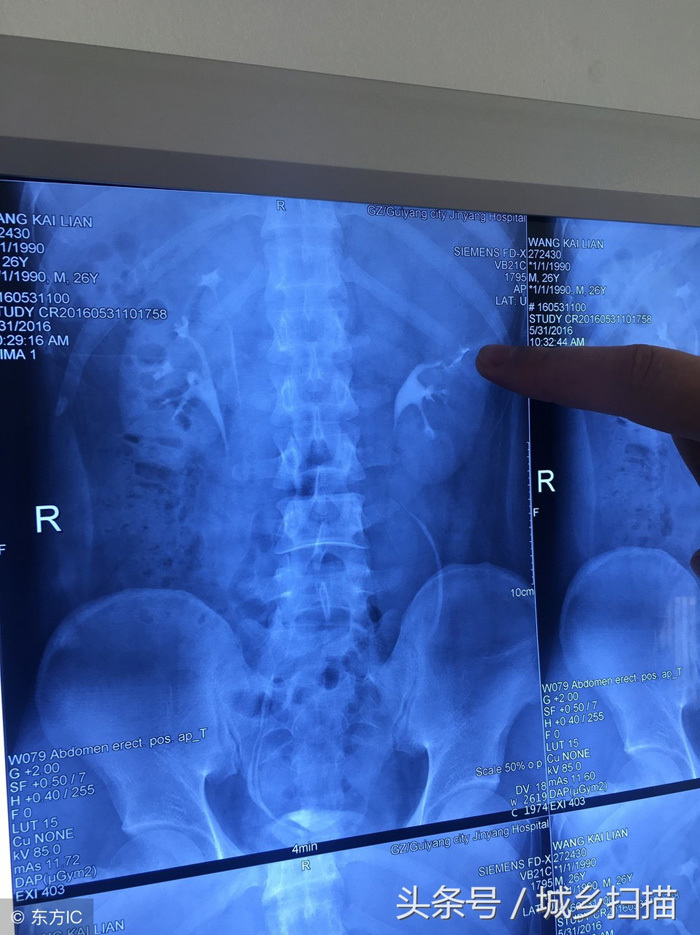

Vương Khai Luyện một lần bị đau dữ dội ở phần lưng eo, vì không chịu nổi mới đến bệnh viện kiểm tra. Sau khi kiểm tra, chụp X quang các bác sĩ phát hiện anh Vương có 4 quả thận. Bác sĩ cho biết, thận trên bên trái của anh bị ứ nước nghiêm trọng, bao phủ và chèn ép thận dưới bên trái, kèm theo nhiễm trùng gây ra một loạt các triệu chứng như đau lưng eo và sốt.

Kết quả chụp X-quang khiến bác sĩ phải bất ngờ

Vương Khai Luyện có 4 quả thận, mỗi bên 2 quả, mỗi bên có hệ thống cung cấp máu và hệ thống bài tiểu. Hai quả thận ở mỗi bên dài như một em bé dính liền. Thận của một người bình thường có kích thước tương đương với nắm tay của người đó. Bốn quả thận của Vương Khai Luyện nhỏ hơn người bình thường và chỉ bằng cỡ nắm tay của em bé.

Bác sĩ nói rằng, thận của Vương Khai Luyện xuất hiện ổ bệnh là thận trên bên trái, bên trong có chứa lượng lớn chất lỏng. Theo kết quả kiểm tra hình ảnh, tràn dịch đã khiến thận trở nên to gấp 3 đến 5 lần so với ban đầu. Nếu thận trên bên trái không được loại bỏ kịp thời, đồng thời nhiễm trùng sẽ càng nghiêm trọng hơn và cũng có thể gây nguy hiểm cho các thận khác.